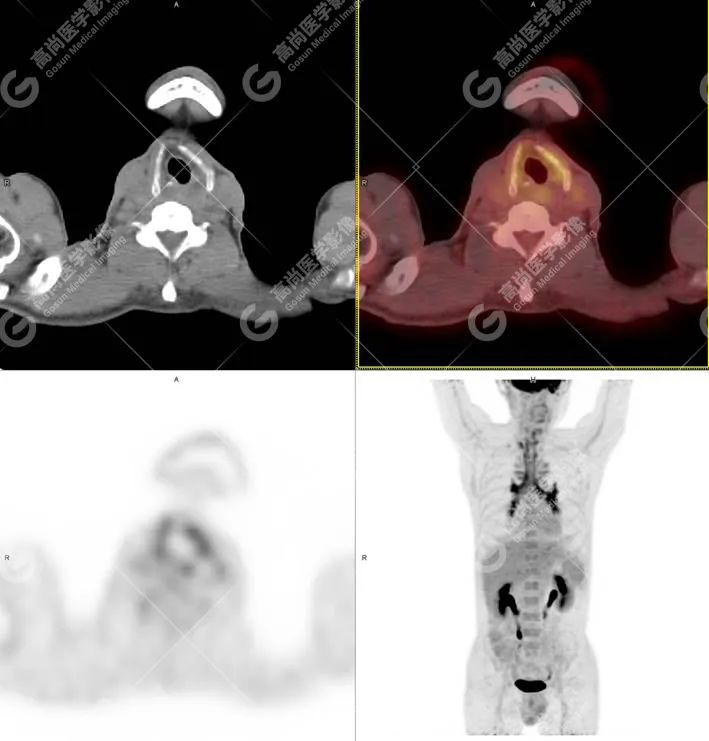

PET/CT 图像

PET/CT 检查所见: 甲状软骨、杓会厌软骨、环状软骨、气管软骨、双侧主支气管及其分支(累及双侧肺叶支气管、部分肺段支气管)管壁弥漫性不均匀增厚,管壁密度增高,其内合并少许条状钙化,管腔见轻度狭窄。气管后膜部受累不显著,气管及支气管未见明显塌陷,放射性摄取弥漫性不同程度增高,SUVmax 3.2-5.6。

PET/CT 诊断: 考虑为复发性多软骨炎。

18 氟-脱氧葡萄糖(18F-FDG)可在炎症组织中积累,使用 18F-FDG PET/CT 评估炎症条件,可用于监测风湿病包括 RP 的疾病活动和治疗反应。RP 患者的 18F-FDG PET/CT 主要表现为受累软骨区域代谢活性增高,因此,18F-FDG PET/CT 有助于 RP 的早期诊断及定位活检部位。

本例中的 J 先生主要表现为气道受累。RP 的气道受累可分为三个阶段:早期炎性肿胀导致气道狭窄,继之气管支气管软骨破坏导致气道塌陷,晚期纤维组织形成气道瘢痕收缩引起气道固定性狭窄。RP 气道病变可迅速进展,可在以呼吸道症状起病者数月内即出现气道塌陷。因此,早期发现 RP 气道受累并给予恰当治疗是抑制气道软骨进行性破坏、改善预后的唯一途径。CT 征象表现为甲状软骨、环状软骨、杓状软骨骨质密度改变、钙化、周围软组织增厚,严重时可引起局部骨质破坏及喉腔狭窄,部分确诊 RP 的患者常规行喉气管 CT 检查发现气道壁增厚、气管剑鞘样改变、与年龄不符的明显气道壁钙化等异常征象,但此例 CT 并无上述征象,导致临床诊断困难。所幸及时进行了 18F -FDG PET/CT 检查,检查中所示支气管壁放射性浓聚,早于呼吸道症状、肺功能异常及 CT 检查异常,并且经激素治疗后支气管壁放射学浓聚可完全消失,亦可用于早期隐匿性气道软骨炎的诊断。

PET/CT 检查一方面可以排除恶性疾病,另外,更重要的是用于早期评估软骨的炎症范围和指导活检。由于软骨的炎症导致病变组织较正常组织摄取氟代脱氧葡萄糖高,通过 PET/CT 检查可大致评估 RP 患者软骨病变的范围,对于病理活检有定位作用,可提高阳性率。因此,全身 PET/CT 检查对于早期诊断有指导意义,能更早发现 CT 检查无法发现的病变,缩短诊断时间。此外,PET/CT 亦能通过对比标准摄取值 ( SUV) 评估疾病活动程度以及治疗方式是否有效。